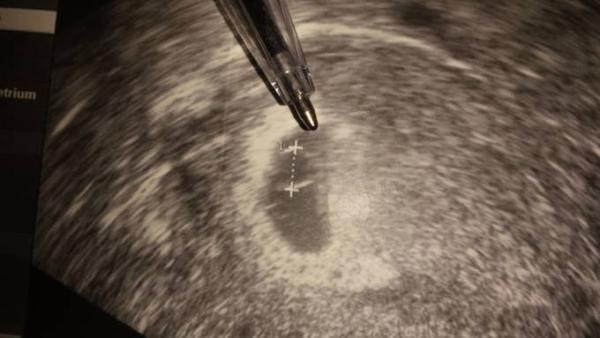

Was meinst du mit Alternative zur Ausschabung? Wenn ich das Bild näher betrachte ist doch rechts neben dem dottersack ein Körper zu erkennen oder nicht????

Ich bin nur ehrlich, dass ich denke, dass es nicht gut aussieht, weil der Embryo zu dem Zeitpunkt schon größer ist als der Dottersack. Da sieht man ihn eig sehr gut.

Ich sehe auf deinem Bild ehrlich gesagt nur den Dottersack. Und der Embryo ist wirklich in dieser Woche schon relativ groß gegenüber dem Dottersack. Ich kann dir bis jetzt nur Vergleichsbilder von meiner letzten Schwangerschaft zeigen. Da siehst du wie es in der Woche eig aussieht. Natürlich drücke ich dir trotzdem die Daumen, dass alles gut ausgeht!!! Versteh mich bitte nicht falsch. Ich wünsche dir natürlich nur das Beste!!! Bild links bei 7+4 Bild rechts bei 8+6